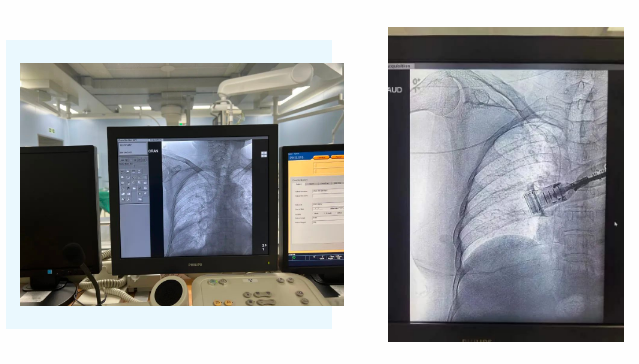

在麻醉手術(shù)中心的配合下,手術(shù)首先由韓海靜護(hù)士長(zhǎng)在超聲引導(dǎo)下應(yīng)用“塞丁格”法穿刺將針尖一樣細(xì)的導(dǎo)絲送入血管,術(shù)中在DSA透視下將導(dǎo)管沿著血管送達(dá)上腔靜脈,尖端精準(zhǔn)定位至上腔靜脈開(kāi)口處。隨后,胸腔外科支亞男主治醫(yī)師在穿刺點(diǎn)下方取2厘米小切口內(nèi)進(jìn)行上臂港囊袋和隧道的制作及導(dǎo)管與港座連接,最后進(jìn)行港體埋植及皮內(nèi)縫合,使患者切口隱蔽美觀創(chuàng)傷小,術(shù)中出血量極少。手術(shù)在X片影像留影,最終手術(shù)順利完成。